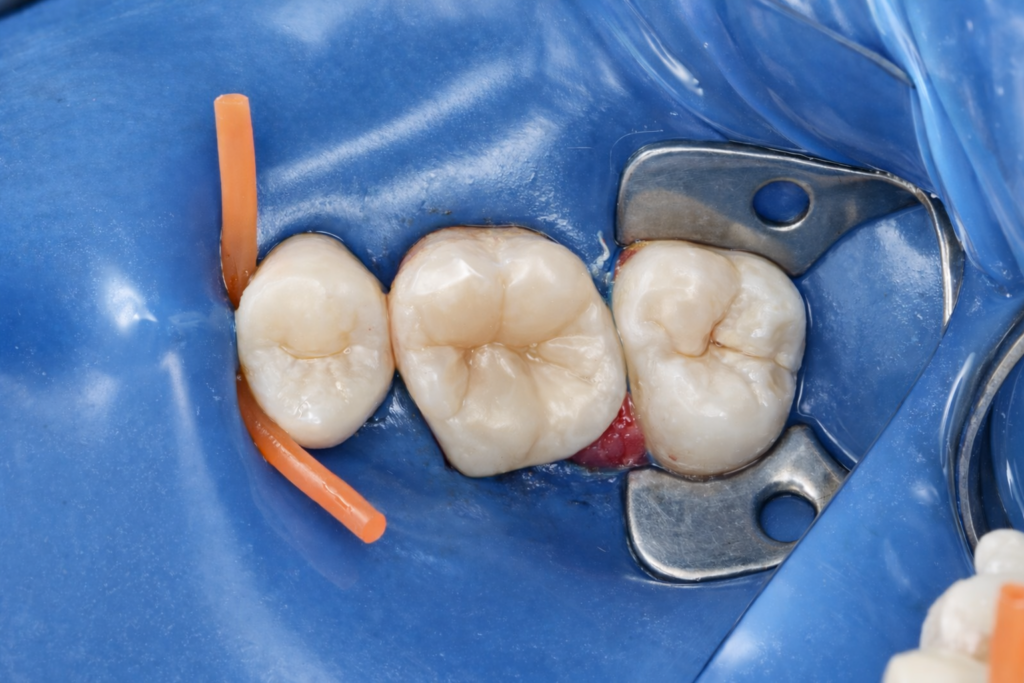

Following endodontic completion, immediate dentin sealing was performed under isolation. Adhesive protocols were selected to maximize bond durability and minimize interfacial degradation.

A biomimetic composite overlay concept was used to restore cuspal integrity. The restoration was built incrementally, respecting natural cusp inclinations, marginal ridge anatomy, and occlusal contacts. This approach allowed:

No unnecessary tooth reduction was performed, maintaining a conservative yet mechanically sound outcome.

Occlusion and Finishing

Occlusion was carefully refined to avoid heavy contacts on weakened cusps. Finishing and polishing focused on smooth margins, anatomical accuracy, and long-term plaque resistance.

The final restoration restored function while maintaining biological respect for the tooth, avoiding the common overtreatment associated with full crowns in similar cases.